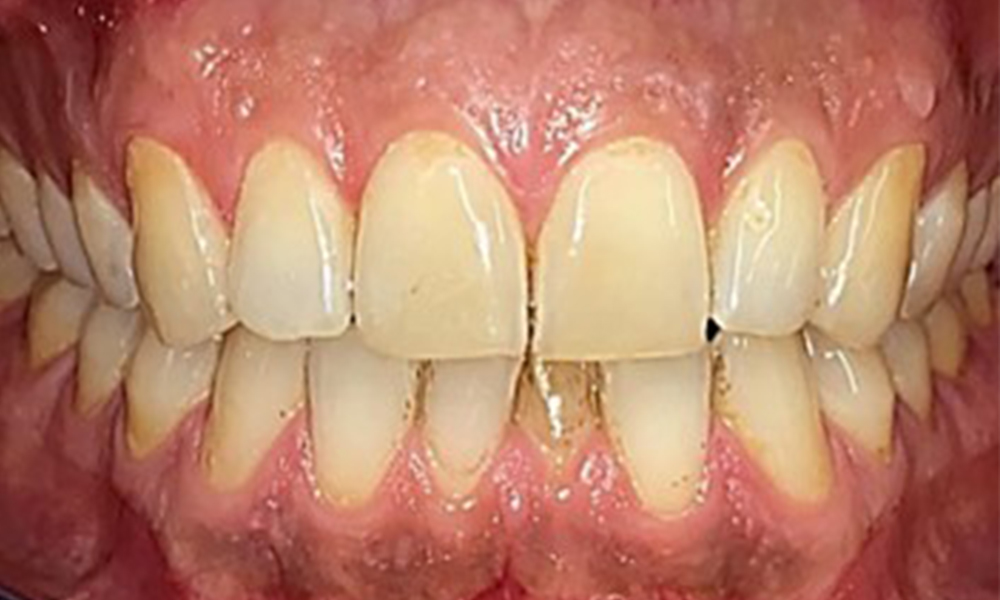

Nu au existat constatări patologice extraorale. În timpul examinării intraorale, în zona frontală, se observă o discolorație maronie în apropierea gingiei keratinizate, precum și la nivelul trecerii la mucoasa mobilă (fig. 2), putând fi atribuite consumului de nicotină. S-au remarcat leziuni albicioase ale mucoasei palatine, îndeosebi în apropierea suprafețelor palatinale ale molarilor maxilari, ceea ce indică o keratinizare crescută, care poate fi atribuită, de asemenea, consumului de nicotină. Limba a fost acoperită cu un strat alb și maroniu amovibil.

Observații la nivel dentar

Pacientul prezintă o dentiție completă, cu 28 de dinți. Se remarcă eroziuni și atriții. (Fig. 4, Fig. 5). Datorită bruxismului, timp de mulți ani, pacientul a purtat gutieră pe timp de noapte. Eroziunile sunt cauzate de consumul prelungit de băuturi izotonice. Nu au fost observate pierderi osoase de natură parodontală sau carii active.